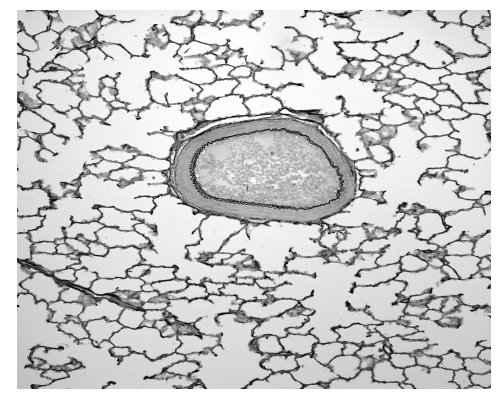

The same microscope was used with a \(\times 40\), instead of a \(\times 10\), magnification objective lens to measure the diameter of an alveolus. The diameter of the alveolus was found to be 96 eyepiece graticule units.

At \(\times 10\) magnification, 10 eyepiece units = 10 stage micrometer divisions = \(10 \times 0.01 \mathrm{~mm} = 0.1 \mathrm{~mm}\). Thus, 1 eyepiece unit = \(0.01 \mathrm{~mm}\) at \(\times 10\). When the magnification increases to \(\times 40\), the apparent size decreases by a factor of 4, so 1 eyepiece unit = \(0.01 \mathrm{~mm} / 4 = 2.5 \mu \mathrm{m}\). The alveolus measures 96 eyepiece units, so its diameter = \(96 \times 2.5 \mu \mathrm{m} = 240 \mu \mathrm{m}\).